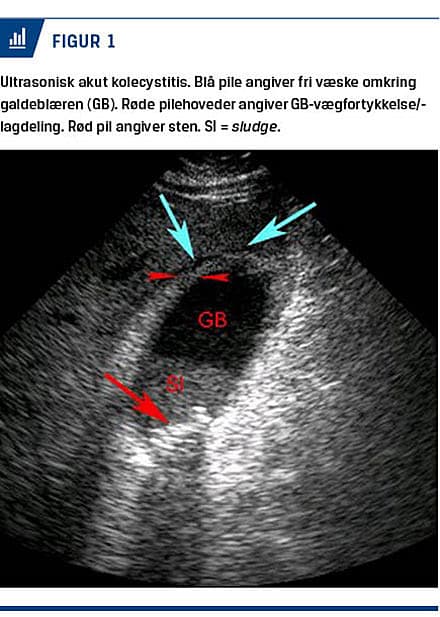

Ultralydskanning af abdomen

UL-skanning af abdomen er den primære billeddiagnostiske undersøgelse til diagnostik af AC [9]. Undersøgelsen er noninvasiv, hurtig at gennemføre og meget velegnet som førstevalgsundersøgelse. De vigtigste ultrasoniske fund er, fraset konkrementer, lagdeling af GB-væggen, GB-vægfortykkelse (≥ 5 mm), væske omkring GB [10] (Figur 1) samt en hyperæmisk væg ved undersøgelse med farve-Doppler [11]. UL-skanning har en sensitivitet på 81% og en specificitet på 83% for evaluering af patienter, hos hvem der er mistanke om AC [12], men det er ofte vanskeligt at påvise sten i de dybe galdeveje [8]. UL-visualisering af GB-sten har

en positiv prædiktiv værdi i kombination med positivt Murphys tegn på 92% og med GB-vægfortykkelse samt lagdeling af GB-væggen på 95% for diagnostik af AC [13]. Sensitivitet for diagnosticering af GB-perforation som komplikation i forbindelse med AC er nedsat og kan tilskrives faktorer som overvægt, akustisk skygge fra sten og artefakter pga. pneumobilia [14, 15].